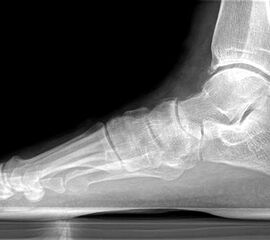

Abbildung Nr. 1: Röntgen Fuß: dp und seitlich stehend.

Es wurden insgesamt 16 Patienten nach dieser Methode operiert, sie erhielten alle das oben genannte postoperative Regime. Der durchschnittliche Nachuntersuchungszeitraum betrug 15 Monate (10-31 Monate), das Patientenalter betrug im Durchschnitt 54 Jahre (48-75 Jahre), das Geschlechtsverhältnis männlich : weiblich betrug 3 : 13. Das durchschnittliche Körpergewicht der Patienten betrug 84kg (66-98 kg). Die Auswertung erfolgte durch die VAS und den AOFAS Score, sowie an Hand der Zufriedenheit der Patienten. Desweiteren wurden die radiologischen Parameter (lateraler talonavicularer Winkel, Saltzmann-Aufnahme und talonavicularer Überdeckungswinkel) prä- und postoperativ ausgewertet sowie die Komplikationen analysiert.

Es konnte, bei präoperativer Unfähigkeit zum einbeinigen Zehenspitzenstand, beim letzten Follow up in 62% der Fälle ein schmerzloser einbeiniger Zehenspitzenstand erreicht werden. Der Saltzmann-Winkel konnte von präoperativ 11° (7-17°) auf 3° (1-8°) korrigiert werden. Der seitliche Metatarsale I Winkel wurde von 18° präoperativ (13-23°) auf 7° (5-13°) postoperativ korrigiert. Der talonaviculare Überdeckungswinkel konnte von präoperativ 10° (4-18°) auf postoperativ 7° (2-15°) reduziert werden.